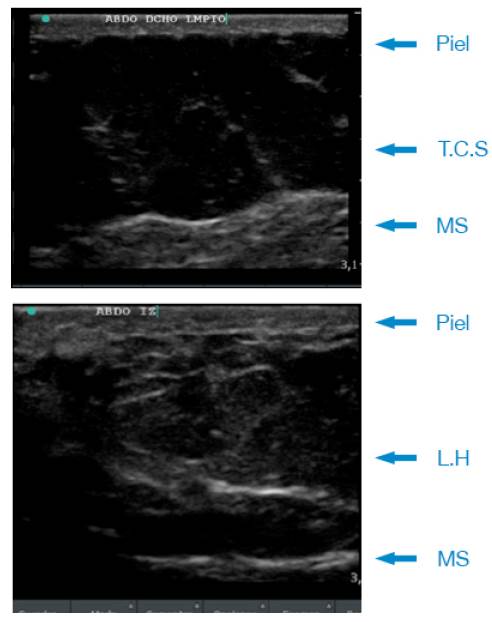

La ecografía de pared abdominal confirmó la presencia de cambios compatibles con LH e infiltración grasa de la pared muscular. La Figura 1 muestra un ejemplo de los cambios específicos evidenciados por ultrasonido e identificados como signos radiológicos para esta entidad 7.

Ultrasonido de lipohipertrofia.

Figura 1: Ultrasonido de lipohipertrofia.

T.C.S: tejido celular subcutáneo; LH: lipohipertrofia; MS: Músculo.

Fuente: Elaboración con base en Blanco et al. 7.